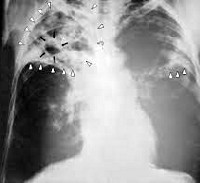

Лечение и осложнения цирротического туберкулеза легких

Цирротический туберкулез легких (ЦТБ) возникает на фоне длительного инфицирования. Некоторые туберкулезные поражения регрессируют, но легочная ткань не восстанавливается. На месте очага разрастается соединительная ткань, образуя толстые волокна коллагена, которые сливаются в нити к корню легкого и плевре. Общая информация Периферический туберкулез легких — одна из форм этого инфекционного заболевания. Согласно Международной классификации болезней, редакция 10 …